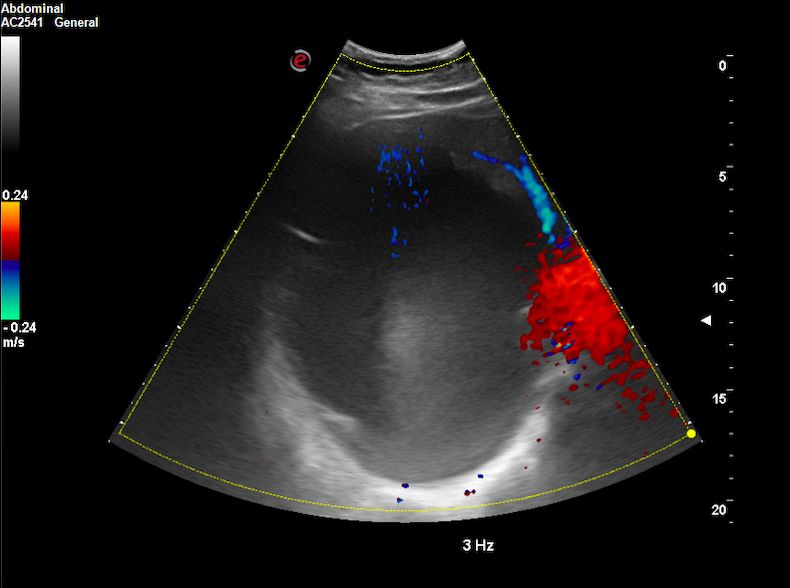

Realizamos ecografía clínica (EC) en nuestro centro de salud, objetivando un quiste de 15 x 12 x 12 cm a expensas de lóbulo hepático derecho, con paredes lisas, refuerzo posterior, contenido anecoico y Doppler-negativo.